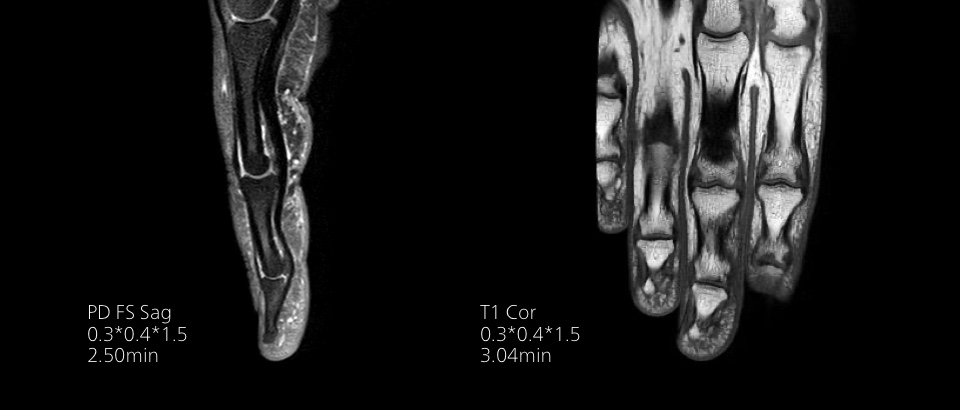

Turn images into answers – 50% faster

Put time on your side with Compressed SENSE to reduce scan time up to 50%2 with virtually equal image quality. Create exceptional MR images with 60% higher resolution for confident diagnosis.

Quality images for quality diagnoses

Our lightest Breeze coils bring extraordinary versatility to imaging challenging anatomies and the smallest joints. A large 55cm field-of-view and premium SNR add to the exceptional image quality.